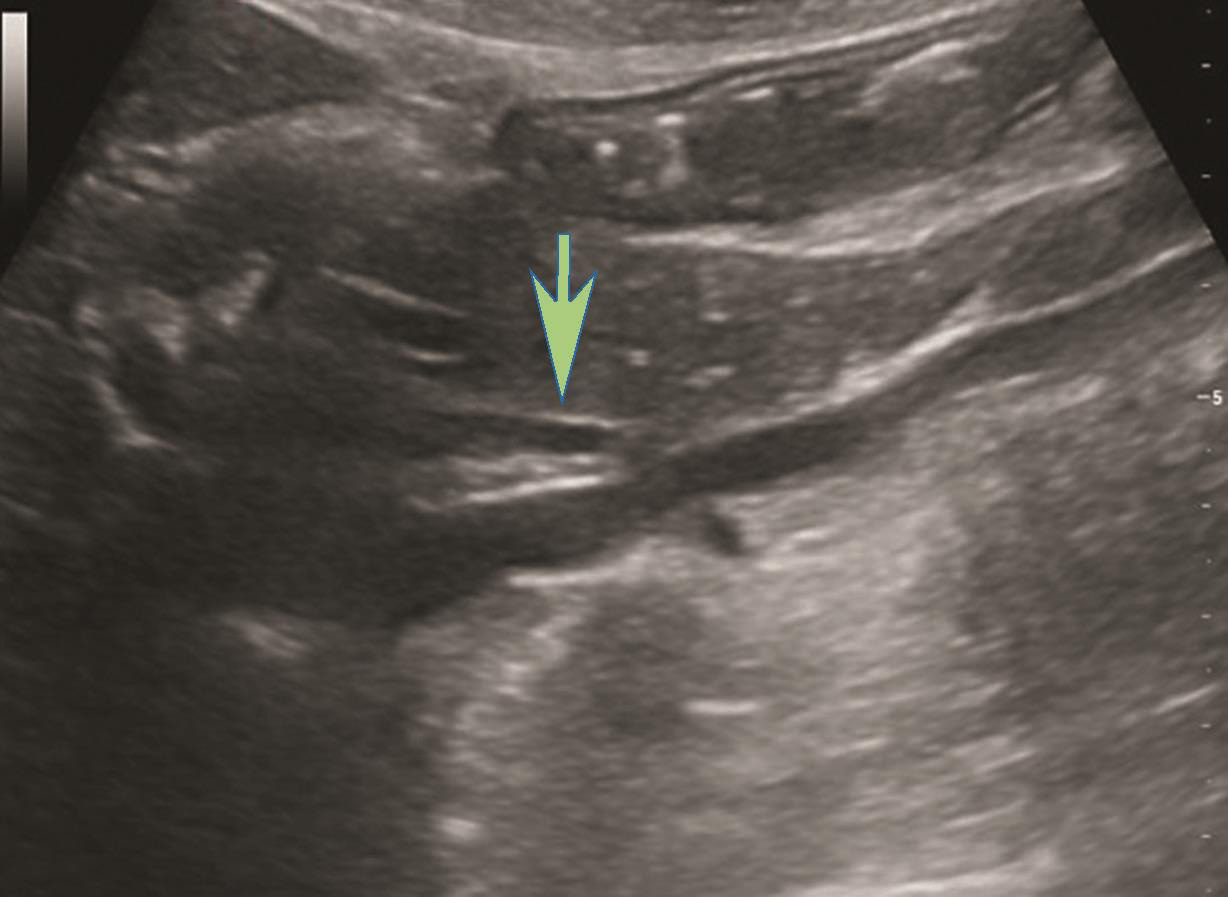

图2-1-4 肝外胆管下段灰阶超声图像

箭头所示为胰头后方肝外胆管下段长轴切面